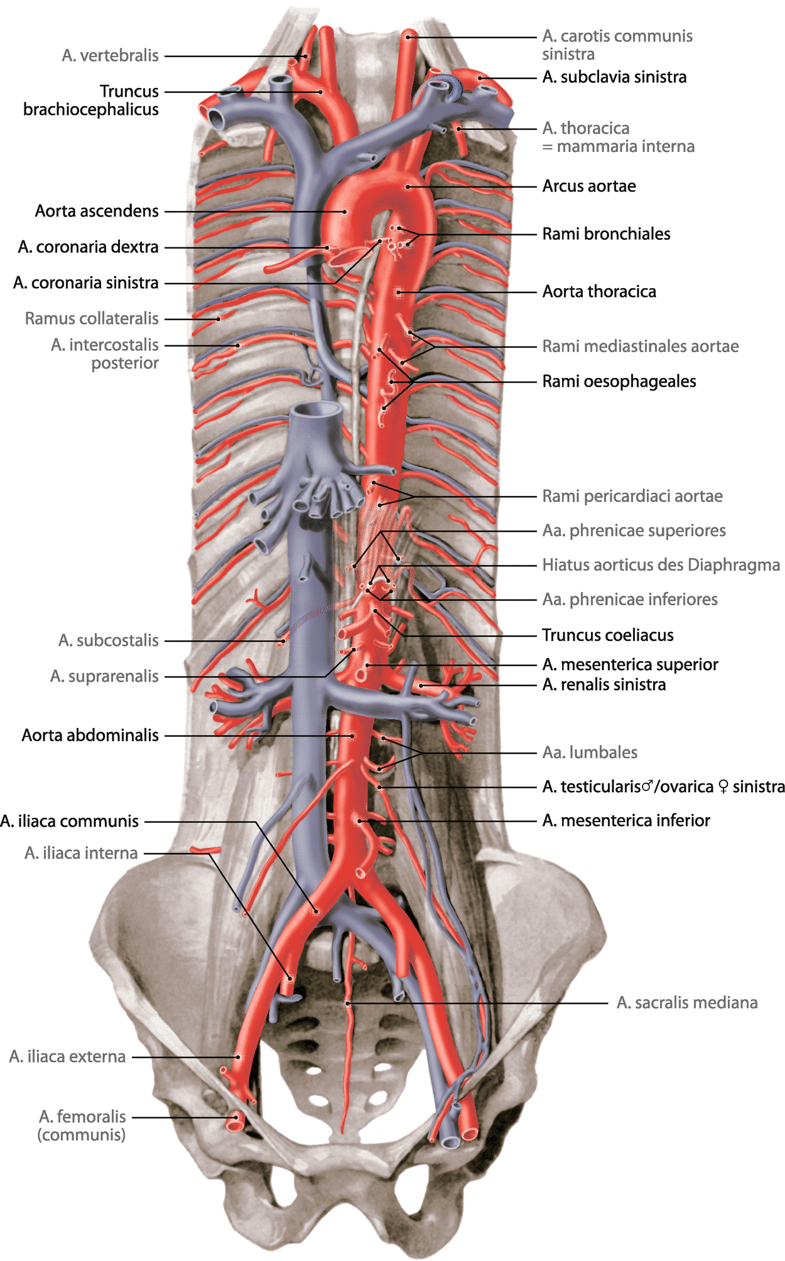

Fig 3.18: Aorta thoracalis descendens

|

|

Fig 3.21: Aorta abdominalis

|

|